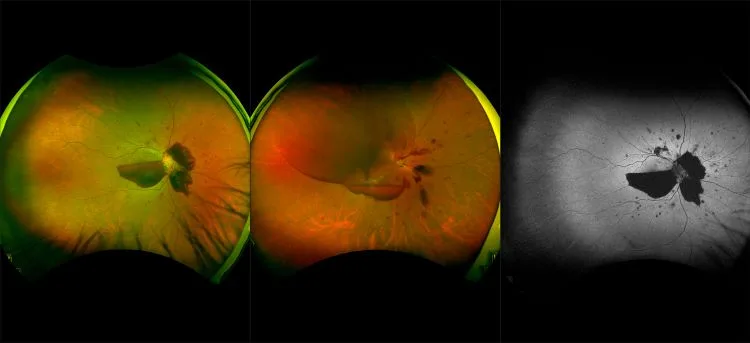

optomap® Recognizing Pathology

This material is designed as a searchable reference resource to support clinical decision-making. The information contained here should be used as general guidance when viewing optomap and OCT images from Optos devices. The differential diagnosis should be made under the direction of the responsible physician. These images were taken on the latest ultra-widefield optomap devices.

optomap Recognizing Pathology is searchable by pathology and/or optomap image modality. You may search by multiples of each selection. Each individual case is represented by the accompanying thumbnail image. Most cases include several different optomap image modalities. To view a full description of the case, please click on the thumbnail. Each image in the case will be made available through our OptosAdvance software which provides multi-dimensional visualization of digital images to aid in the analysis of anatomy and pathology. Support and pathology definitions can be found by selecting one of the buttons, above. Should you have questions, please complete the form below.